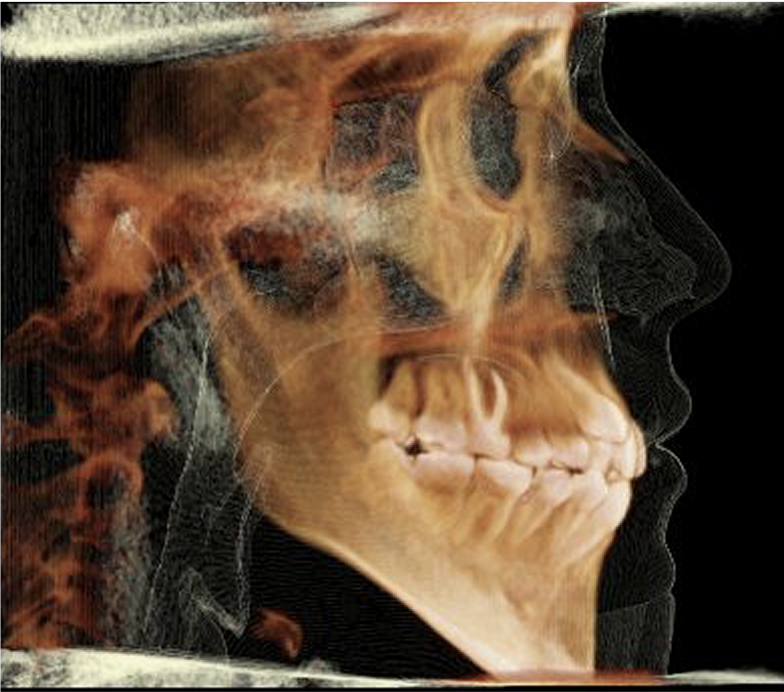

Meet Felix the iCAT! This the name of our 3D X-ray machine. At Buena Vista Orthodontics, we utilize state-of-the-art iCAT 3D imaging technology to provide comprehensive diagnostic capabilities. Nothing hides from us. In 3D, we could capture detailed images of your This advanced cone beam CT teeth, bone, TMJ, airways and much more, giving us a superior diagnostic capabilities.

Why iCAT 3D Imaging? Just look and see for yourself!

The iCAT system visualizes areas that traditional X-rays cannot show, including tooth roots, bone density, airway passages, and TMJ structures. This enhanced imaging enables us to create more accurate treatment plans and identify potential complications early.

Many Views from

One Low-Radiation Xray!